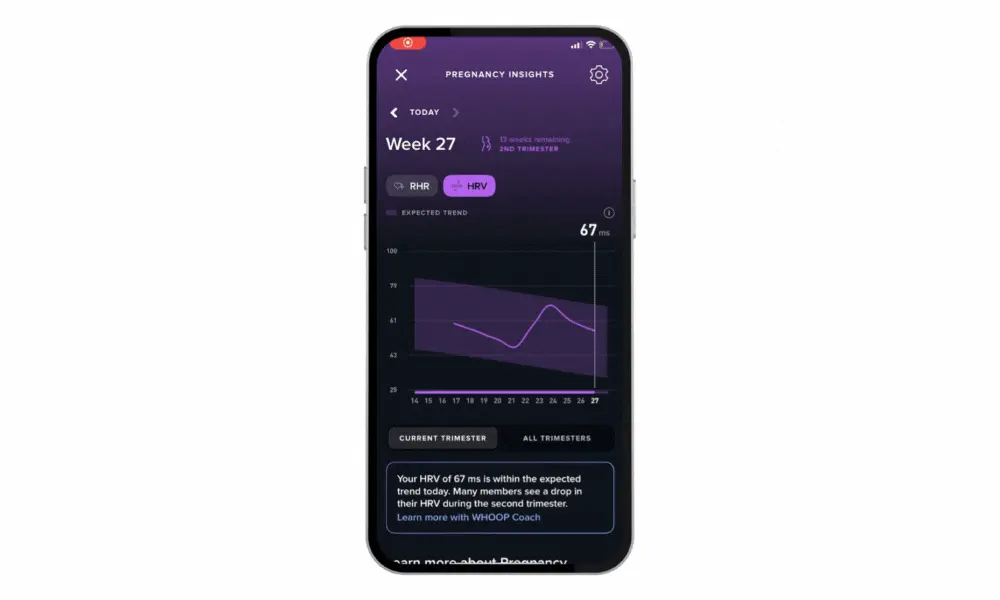

This potentially life-changing discovery led us to develop Pregnancy Insights. With Pregnancy Insights, members will receive personalized postpartum insights up to 12 weeks post-delivery, track RHR and HRV, and more.

Pregnancy is a uniquely challenging journey, and every week is a major milestone. Expectant members can use the Pregnancy Insight feature to input their projected due date from week 5 onwards and begin receiving tailored insights and recommendations. From needing more rest, to increasing hydration, to exercise considerations, Pregnancy Insights sheds more light on the adapting needs of the body. You’ll also be able to track resting heart rate (RHR) and heart rate variability (HRV) trends during every trimester based on their personalized baseline. Given these metrics change significantly throughout the duration of pregnancy, WHOOP will provide trend lines for expectant members to better understand how their own changes compare to what has been seen throughout the course of pregnancy for similar members.